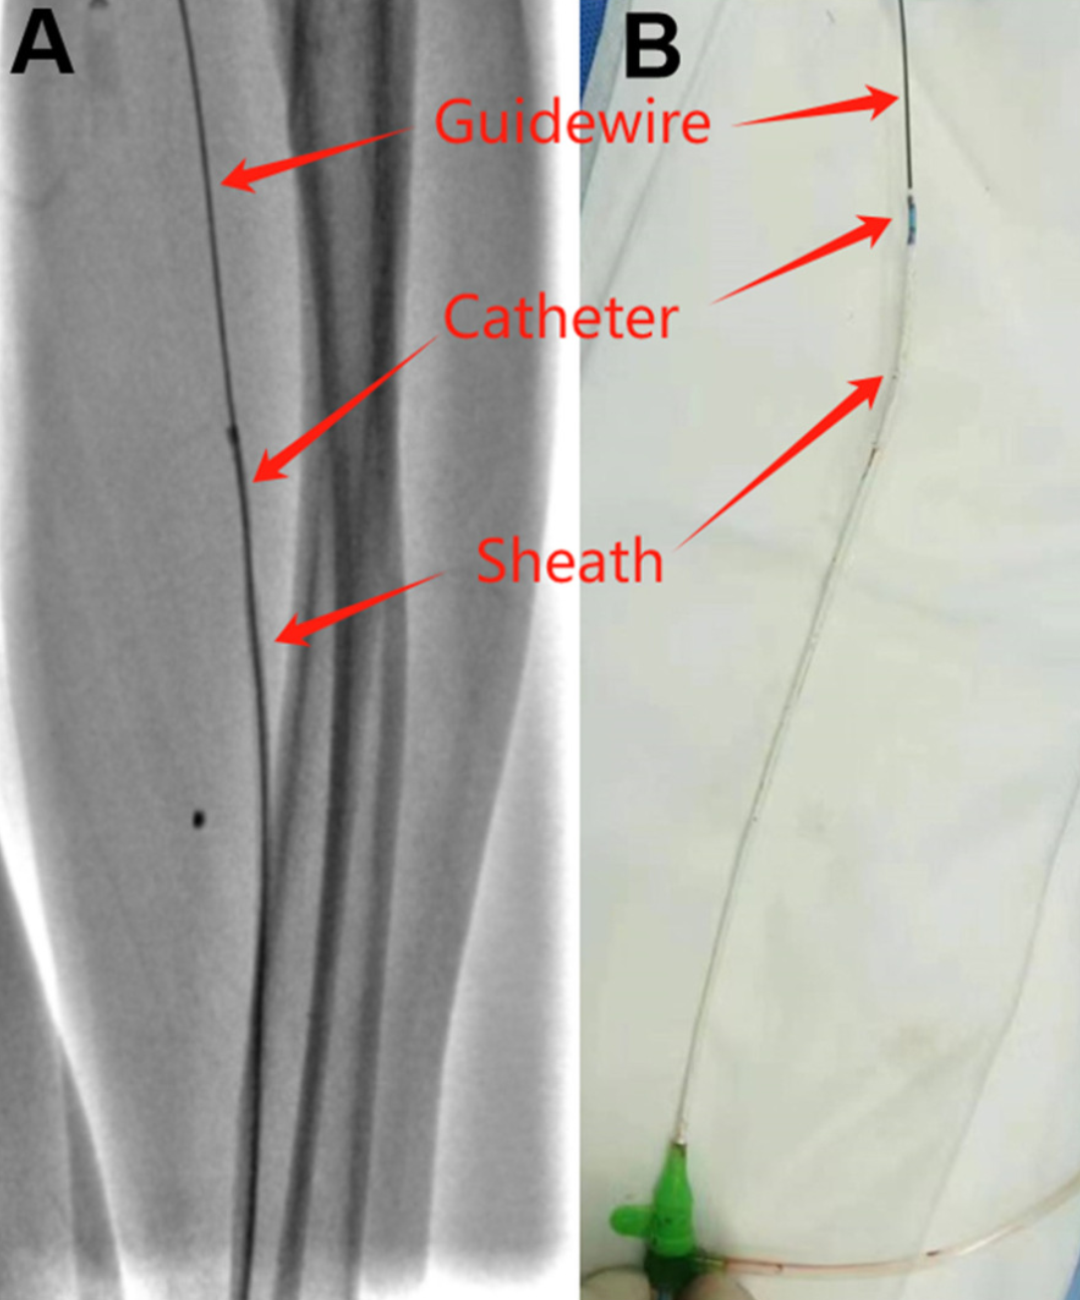

4. 在导丝支撑下将5F JR3.5导管送入已拉伸变形的鞘管,形成"导丝-导管-鞘管"整体结构

5. 在导丝和导管的辅助下,缓慢整体撤出系统

(A)透视下“导丝-导管-鞘管”整合 (B)体外展示“导丝-导管-鞘管”整合系统